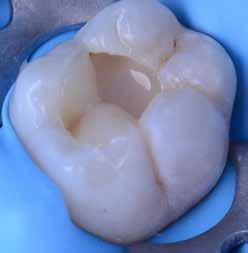

Az 53 éves hölgy páciens jobb felső 6-os fogában látható amalgámtömés cseréje volt a cél. A tömés mellett secunder caries és az amalgám következtében létrejött mesialis zárólécen áthaladó repedés, továbbá mesialis caries figyelhető meg (1. ábra). El kellett kerülni, hogy a tömés kifúrásakor az amalgámtörmelék a páciens szájába kerüljön, esetleg ebből valamennyit lenyeljen, a kezelés első lépésként kofferdám izoláció került fel a jobb felső kvadránsba (2. ábra). A kapocs a 1.7 fogra került, ezzel kényelmesen helyet teremtett a későbbiekben felkerülő matricarendszernek. Az egyszerre több fog izolálása lehetővé teszi, hogy a szomszédos fogak referenciául szolgáljanak a restauráció felépítése közben.

A régi amalgámtömés eltávolítását követően caries indikátor segítette a carieses laesio megfelelő kitisztítását a pulpa expozíciója nélkül. Ezután kerülhetett sor az ideális üregdesign kialakítására, továbbá a zománcszélek finírozására (3. ábra) Az approximális box megnyitása során az alátámasztatlan zománcprizmák eltávolításra kerültek, ezzel is csökkentve a secunder caries képződés veszélyét. Az így kialakuló forma elősegíti a matrica megfelelő adaptációját, végül pedig az approximális box határainak a hozzáférhetőségét, így finírozás során ez jobban kontrollálható és polírozható.

A Palodent V3 matricarendszer felhelyezését követően a zománc 10 másodperces szelektív savazása, majd lemosása és leszárítása után történt a kavítás bondozása Prime & Bond Universallal.

Kulcslépés: a II. osztályú üreget a matricarendszer segítségével I. osztályúvá lehetett átalakítani.

A pontosabb széli záródás érdekében célszerű a matrica illesztési határába némi folyékony kompozitot felvinni (NeoSpectra ST flow A2), majd megvilágítás nélkül a zárólécet paszta kompozittal (NeoSpectra STHV A2) felépíteni, miközben a kifolyó fölösleges folyékony kompozit eltávolításra kerülhet. Így ki lehetett használni és kombinálni a két különböző konzisztencia előnyeit.

A polimerizációt követően kerülhet sor a matricafeszítő gyűrű, valamint a matrica eltávolítására. A Palodent V3 fülekkel ellátott matrica kialakításának és a speciális PinTweezers csipesznek hála, a feszes kontaktpont ellenére a matrica könnyedén eltávolítható. Az éket viszont a kezelés végéig

célszerű bennhagyni, elkerülve egy esetleges nemkívánatos vérzést (4. ábra)

A matrica és gyűrű nélkül az approximális fal magassága, valamint a szomszédos fogakhoz viszonyítható dimenziók jobban megállapíthatóak. A jobb térlátás és a nagyobb mozgástér precízebb eredményhez vezet, csökkentve ezzel az utólagos finírozás mértékét, továbbá a részletgazdagon kialakított anatómiai struktúrák torzulásának az esélyét. Az üreg mélyebb részei SDR Plus A3-mal kerültek feltöltésre, majd NeoSpectra STLV A3-mal kiegészítve vált teljessé a dentin pótlása (5. ábra), ezzel létre lehetett hozni egy homorú formájú kromatikusabb alapot.

Ezt követően csücsökről csücsökre haladva a felső hatosokra jellemző anatómiai struktúrák, megfelelő orientációval bíró csücsöklejtők és elsődleges barázdák Neo Spectra

HV A2 anyagból kerültek kialakításra (6. ábra). Apró „kompozit-hurkákkal” kiegészítve létrehozható a csücskökön belüli tagoltság, ezzel kialakítva a másodlagos barázdarendszert és egy sokkal kidolgozottabb anatómiai struktúrát (7. ábra). A fogorvos esetleges „művészi hajlamát” is figyelembe véve, a természethű megjelenés barázdafestéssel (Micerium - Stain Brown 2) még tökéletesebb lehet (8. ábra). Ezzel a korábban részletgazdagon kialakított ba-

rázdarendszer kiemelhető, és optikailag fokozható a gödröcskék mélysége is.

A restauráció megfelelő polimerizációja után célszerű a kofferdám nyújtotta retrakciót kihasználni, és a restauráció széli záródásában levő esetleges kompozitfölösleg elfinírozását jobb rálátás mellett elvégezni (9. ábra). Ebben nagy segítségünkre lehet az Enhance rendszer, mely a kompozitot nagyon szépen elsimítja, de a természetes fogszövetet nem bántja.

A matricázott terület széli záródásának a kidolgozásában az EVA polírozó (10. ábra) lehet a segítségünkre, amellyel a gingiva sérülése megelőzhető, és a kialakított feszes kontaktpont sem kerül redukcióra (11-12. ábra)

A kofferdam eltávolítását követően kerülhetett sor az occlusio beállítására csücsöklejtők domborúságának a redukciója révén (13. ábra). A harapás gyémántfúrókkal történő beállítása után a polírozás Enhance rendszerrel történt, melynek végső lépéseként a PrismaGloss használatával (14. ábra) nyerhette el a restauráció a végső fényességét (15. ábra)

A ma rendelkezésre álló modern eszközöknek és anyagoknak hála II. osztályú üregek direkt módon kiszámíthatóan restaurálhatóak. A matricarendszernek köszönhetően helyreállítható a feszes kontaktpont, a „kaméleon effektussal” bíró kompozit pedig a tömés integrációjáért felel. A megfelelő adhézió, a precízen kidolgozott széli záródás és a plakkréteg megtapadását nehezítő polírozott felszín a kezelés hosszú távú sikerének a garanciája. Mindezek együtt egy hosszú távon tartós, funkcionális és esztétikai rehabilitálást tesznek lehetővé.